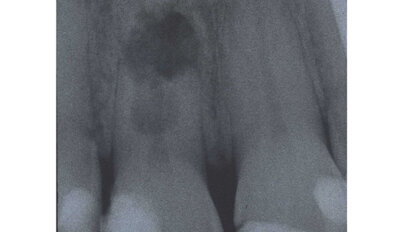

Case report: Internal root resorption rules out restoration

For decades, case reports and scientific studies have described the condition of internal root resorption. A recent web search related to internal root ...